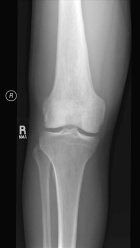

Case 6

T.C. - 40 year old male with a painful and enlarging thigh mass

Zoom image: Radiological image Radiological image.